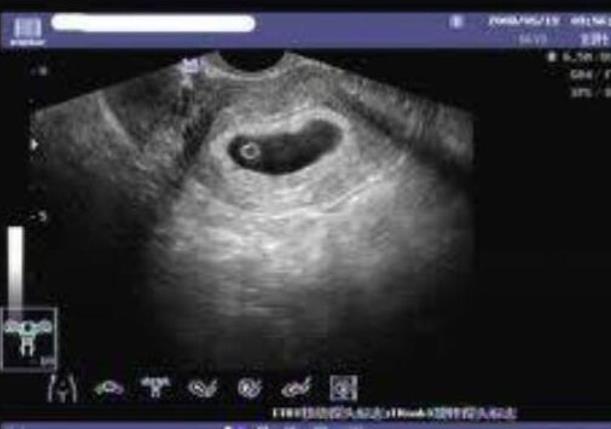

一般,医生会在移植前,检查你的雌二醇值、子宫厚度,如果不达标的话是不会手术滴!所以,你已然移植了,证明一切检查值是正常的。另外,成功受孕的关键是:子宫厚度(8-12CM)、雌二醇值(会在移植后产生孕激素,维持合适的子宫厚度供胚胎着床)、孕酮值(越高越好,促进胚胎着床与发育)试管本来成功率就不及外界宣扬的那么高。一般要尝试二次以上,一次的成功机率太小了。移植后,头四天卧床休息,后面就要开始适度活动,但不能太劳累,如果出现腰酸、子宫坠痛要及时休息。其实,除了人力因素外,关键还是看胚胎自己,如果它能着床,且质量过关,就大功告成了。放轻松点!